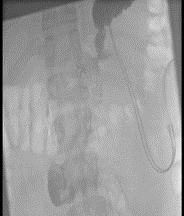

Upon arrival, laboratory studies revealed severe malnutrition according to CONUT, anemia, and leukocytosis. Parenteral nutrition was initiated with Kaviben solution (1700 kcal in 2700 mL), starting at 100 mL over 24 hours, and the patient remained NPO. The patient received a total of four units of packed red blood cells for anemia. A subsequent esophagogastroduodenal series did not reveal any leak (Figure 1). Despite these measures, the patient continued to have serobilious drain output, nausea, and persistent vomiting. Follow-up CT imaging confirmed prior findings, without evidence of active leakage.

Figure 1: Initial gastroesophageal series: The gastric pouch showed postsurgical changes from bariatric surgery, without evidence of extrinsic compression. There was adequate passage of contrast into the intestinal tract, with delayed emptying, no leakage, and normal transit of the contrast material.